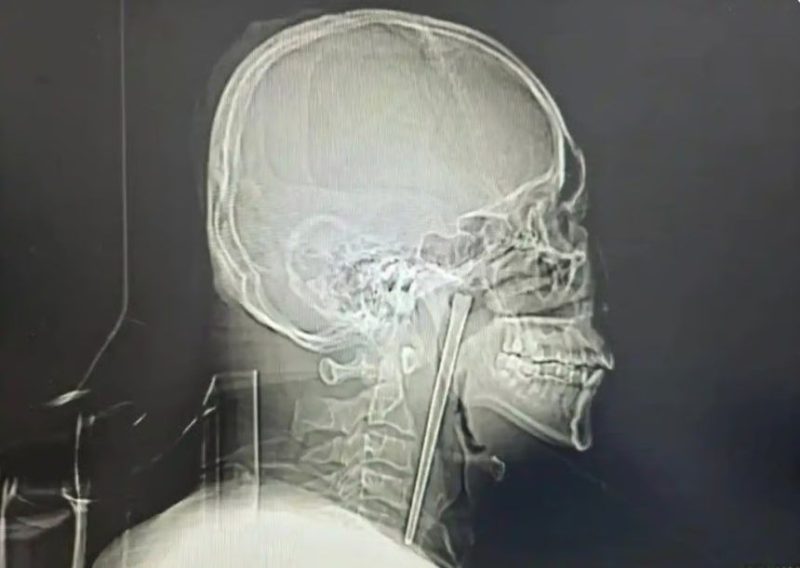

정밀 검사 결과 왕씨가 삼킨 젓가락은 목 안쪽 연구개 부위에 박혀 있었던 것으로 확인됐다. 의료진은 다행히 주변 점막에 손상이 없고 성대 기능 역시 정상적으로 유지되고 있었다고 설명했다.

왕씨는 목 절개를 거부했고 의료진은 구강을 통한 최소 침습 수술을 진행했다. 다행히 젓가락은 성공적으로 제거됐다. 왕씨는 빠르게 회복해 수일 뒤 퇴원했다.